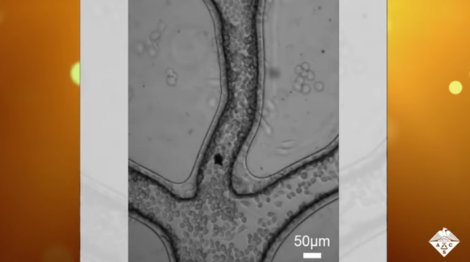

Os robôs desenvolvidos pelos médicos Jiawen Li, Li Zhang, Dong Wu podem aplicar o medicamento apenas nas partes necessárias, o que reduz as chances de complicações. Os modelos são feitos em 4D a partir de um hidrogel responsivo ao pH. O 4D se baseia na mesma ideia do 3D, no entanto, nesse caso são objetos 3D que podem mudar de forma.

Foram testados microrrobôs de três animais diferentes: borboleta, peixe e caranguejo. Em cada um, a mudança é diferente: caranguejos abrem as pinças, peixes a boca e borboletas, as asas. Depois de impressos, os robôs são mergulhados em uma solução de nanopartículas de óxido de ferro que os tornam magnéticos. A intenção é testar para ver qual formato é mais eficiente na realização do trabalho.

Apesar de promissora, a pesquisa ainda deve passar por muitas etapas antes dos testes em humanos. É necessário ainda reduzir o tamanho dos microrrobôs, apesar de “micros” ele vão precisar ser ainda menores para conseguirem viajar pela corrente sanguínea.